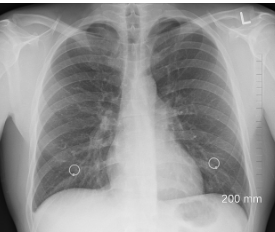

사인은 폐기흉(기흉)으로 알려졌으며, 고인은 지난 7월에도 기흉 관련 시술을 받은 뒤 산소호흡기에 의존해 생활해 왔습니다.

폐기흉은 폐의 공기주머니(폐포)가 터지면서 공기가 흉막강으로 새어 나와, 폐가 수축되는 질환입니다.

정상적으로는 폐가 공기를 들이마시고 내쉬면서 팽창과 수축을 반복하지만, 흉강 내 압력이 높아지면 폐가 펴지지 못해 호흡 곤란을 유발합니다.

전유성 씨의 경우, 과거 폐렴 이력이 있었고 고령으로 인해 폐 기능이 약화된 상태에서 폐기흉이 치명적으로 작용한 것으로 추정됩니다.